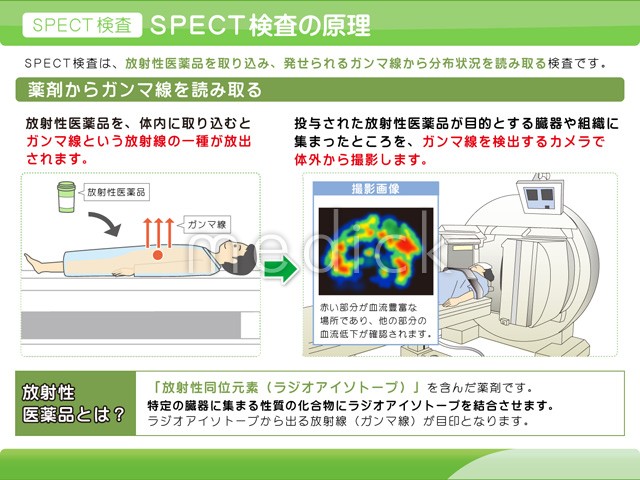

spectの画像

![spect 撮って診る認知症genki55.net|SPECT検査[認知症の進行状況がわかる]](http://genki55.net/img/spect09.gif)